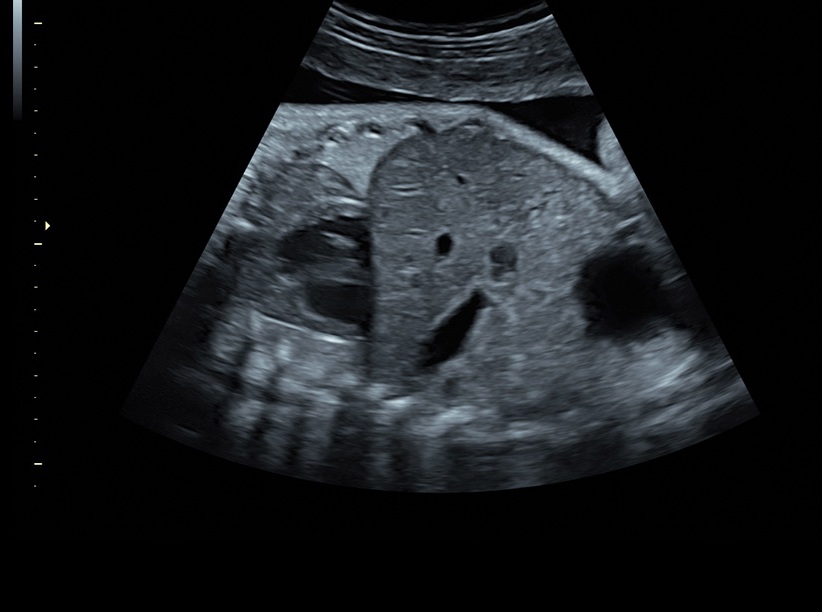

• Сложные инструменты для оценки качества плода: Сканер оснащен инновационными инструментами, позволяющими проводить детальную оценку состояния плода, включая его сердечную деятельность, анатомию и кровоток.

• Технология SonoRenderlive: Эта технология облегчает получение 3D/4D изображений путем автоматического изменения положения плоскости визуализации в зависимости от движений плода. Она позволяет получить реалистичные и объемные изображения, что полезно для демонстрации плода будущим родителям и для дополнительного анализа.

• Высокое качество изображений: Voluson S8 обеспечивает высококачественные изображения, позволяющие детально оценить состояние плода и обнаружить возможные патологии.

• Стандартизованные измерения толщины воротникового пространства и IV желудочка головного мозга плода в I триместре беременности (SonoNT и SonoIT): Эти технологии позволяют в полуавтоматическом режиме измерять толщину воротникового пространства и размеры желудочка головного мозга плода в первом триместре беременности, что помогает в ранней диагностике возможных аномалий.